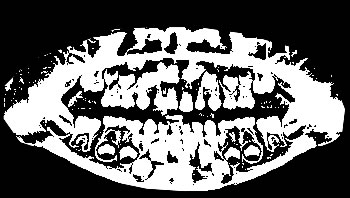

Figure 4: Annotation of the teeth.

Image annotation

The process of annotating the images of our proposed data set occurred in two parts. First, it was initiated by the upper jaw through the annotation of the third right upper molar and making the annotation of all the teeth of the upper arch to the third left upper molar. Then, the same process was performed on the lower jaw with all the teeth, and in the same direction as the upper jaw, from left to right, starting with the annotation of the third right lower molar, and annotating all teeth from the lower arch to the lower third molar. Figure 4 illustrates the tooth annotation process through a panoramic X-ray image of the data set.